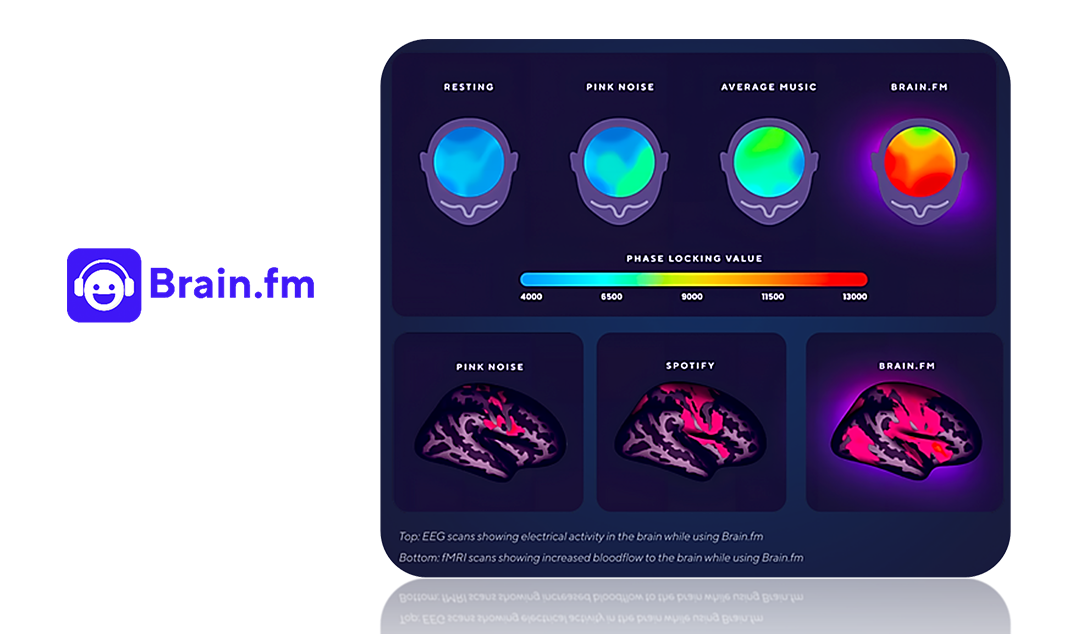

Innovation is also flourishing among startups dedicated to AI-powered neuroscience. Companies like Brain.fm create adaptive soundscapes that help users improve focus and relaxation.

Figure 4 Time Magazine's Best Inventions of 2018.